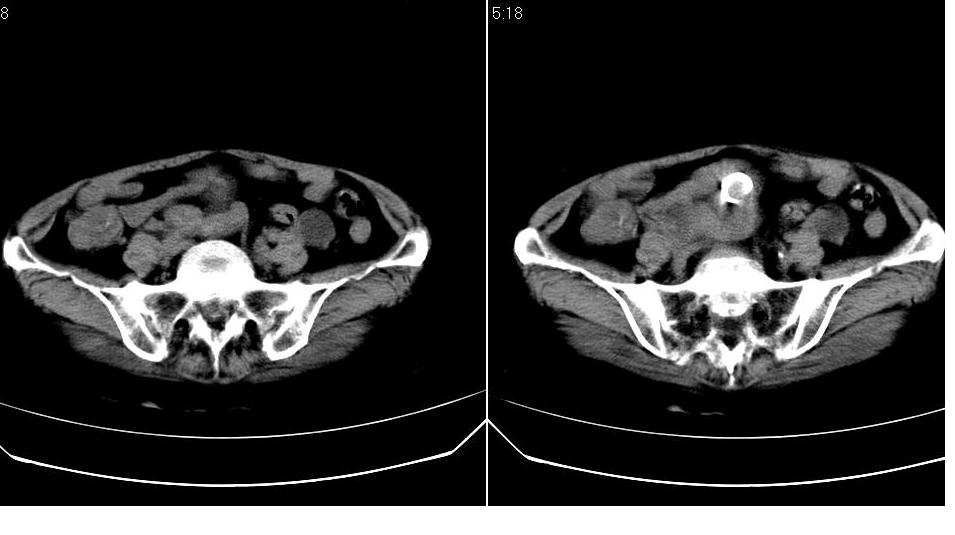

女,70岁,十天前在上级医院确诊宫颈癌,具体病史不详。

子宫形态增大,其内密度不均匀,宫颈部未见异常

子宫形态增大,其内密度不均匀,宫颈部未见异常,建议增强。

子宫体积增大,其内密度不均,考虑子宫内膜癌侵犯宫颈

宫颈癌阻塞性宫腔积液?累及宫腔?